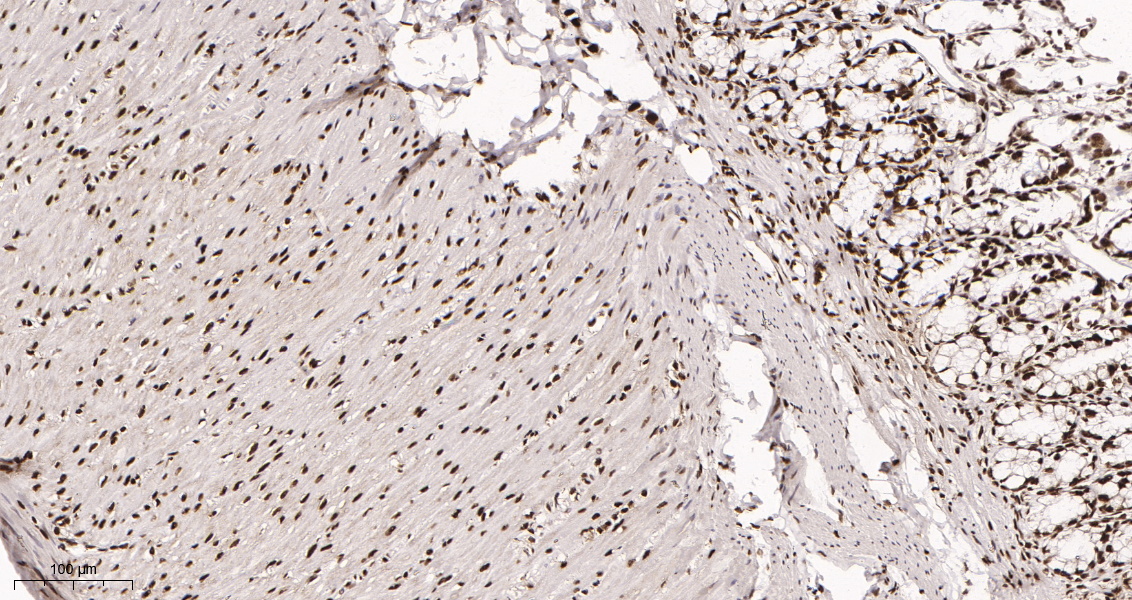

产品名称HDAC2 (10B14) Rabbit Monoclonal Antibody

推荐应用WB,IHC-P,IF-P,IF-F,IF-ICC,IP,ELISA

稀释度IHC-P 1:200-500,WB 1:1000-5000,IF-P/IF-F/IF-ICC 1:200-1000,ELISA 1:5000-20000,IP 1:50-200

背景介绍This gene product belongs to the histone deacetylase family. Histone deacetylases act via the formation of large multiprotein complexes, and are responsible for the deacetylation of lysine residues at the N-terminal regions of core histones (H2A, H2B, H3 and H4). This protein forms transcriptional repressor complexes by associating with many different proteins, including YY1, a mammalian zinc-finger transcription factor. Thus, it plays an important role in transcriptional regulation, cell cycle progression and developmental events. Alternative splicing results in multiple transcript variants. [provided by RefSeq, Apr 2010],